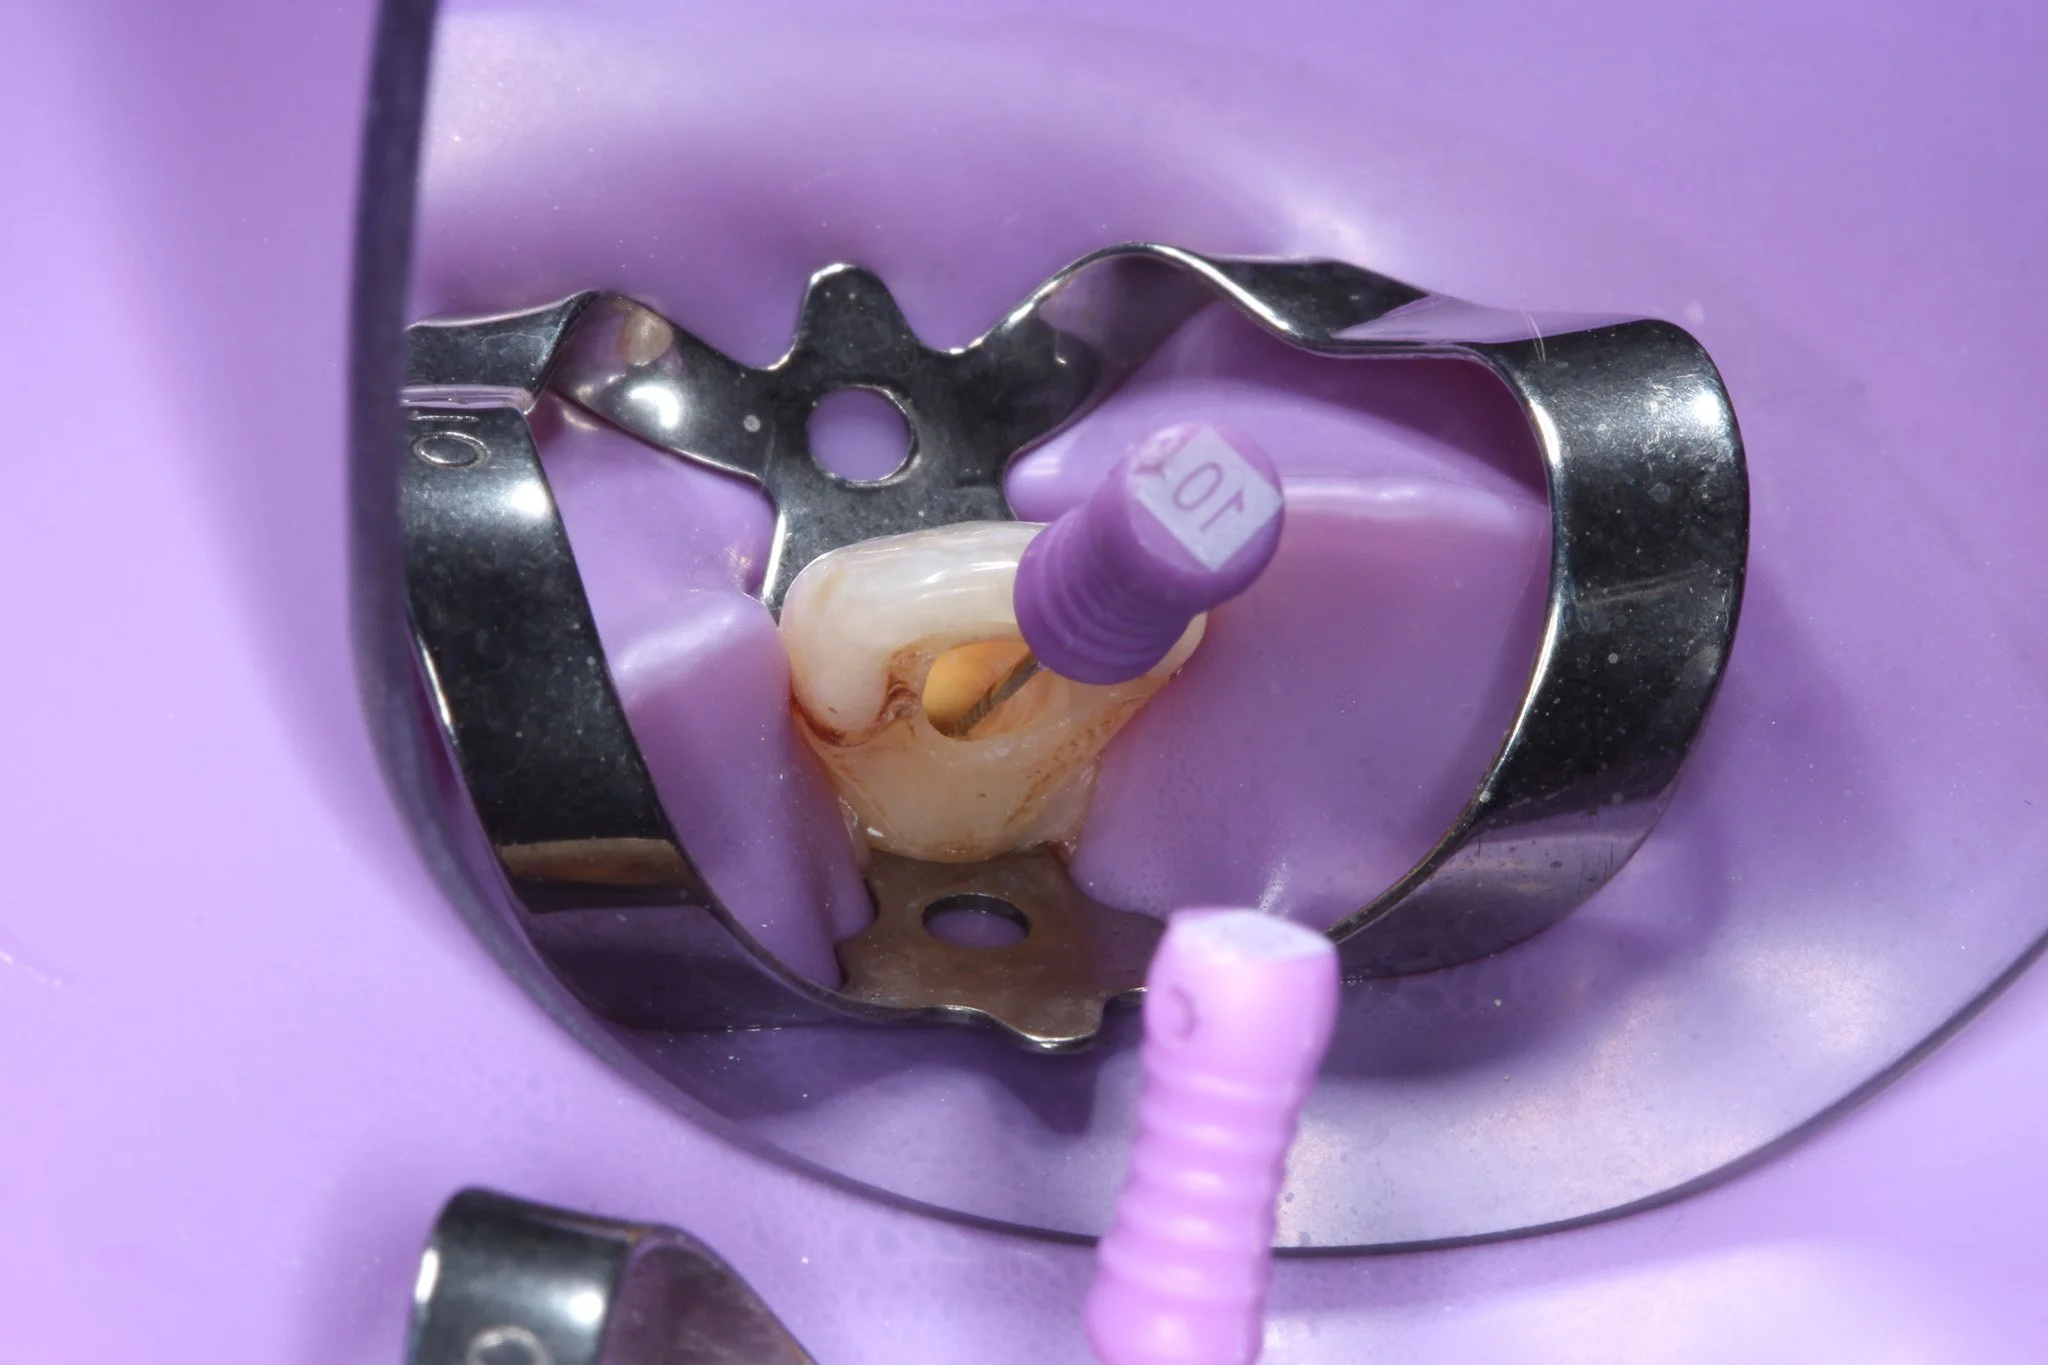

A dental procedure with a metal clamp around a tooth on a purple background.

Dental procedure with a tooth, a rubber dam, and a dental clamp on a purple background.

Dental procedure featuring a tooth with a rubber dam and a syringe with anesthetic.

Using very fine instruments, the dentist will carefully remove the soft tissue (pulp) from the chamber and root canals. This includes removing bacteria and dead or inflamed nerve tissue that’s causing the pain.

Once the pulp is removed, the canals are flushed with an antibacterial solution (like sodium hypochlorite or chlorhexidine) to help eliminate any remaining bacteria. This reduces inflammation and promotes healing.